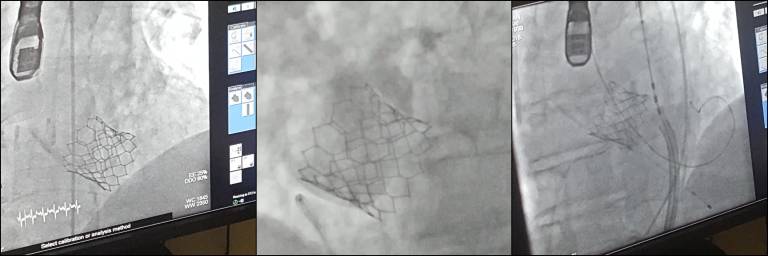

V torek so v UKC Maribor, v katetrskem laboratoriju Oddelka za kardiologijo in angiologijo, uspešno izvedli prvo nekirurško vstavitev aortne zaklopke.

S tem, z uvedbo tovrstne metode, se v Univerzitetnem kliničnem centru Maribor povečuje dostopnost in obenem omogoča enaka kvaliteta zdravljenja pri bolnikih z okvaro aortne zaklopke tudi v severovzhodni Sloveniji.